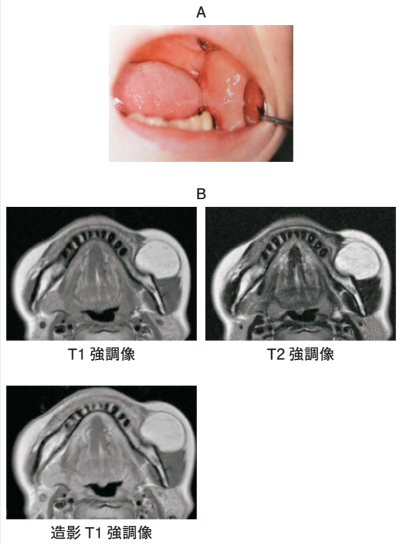

53 歳の女性。頰部の腫脹を主訴として来院した。初診時の口腔内写真とMRI T1 強調像、T2 強調像および造影T1 強調像を別に示す。病変の CT 値(HU)はどれか。1つ選べ。

a. -1,000

b. -100

c. 0

d. 200

e. 500